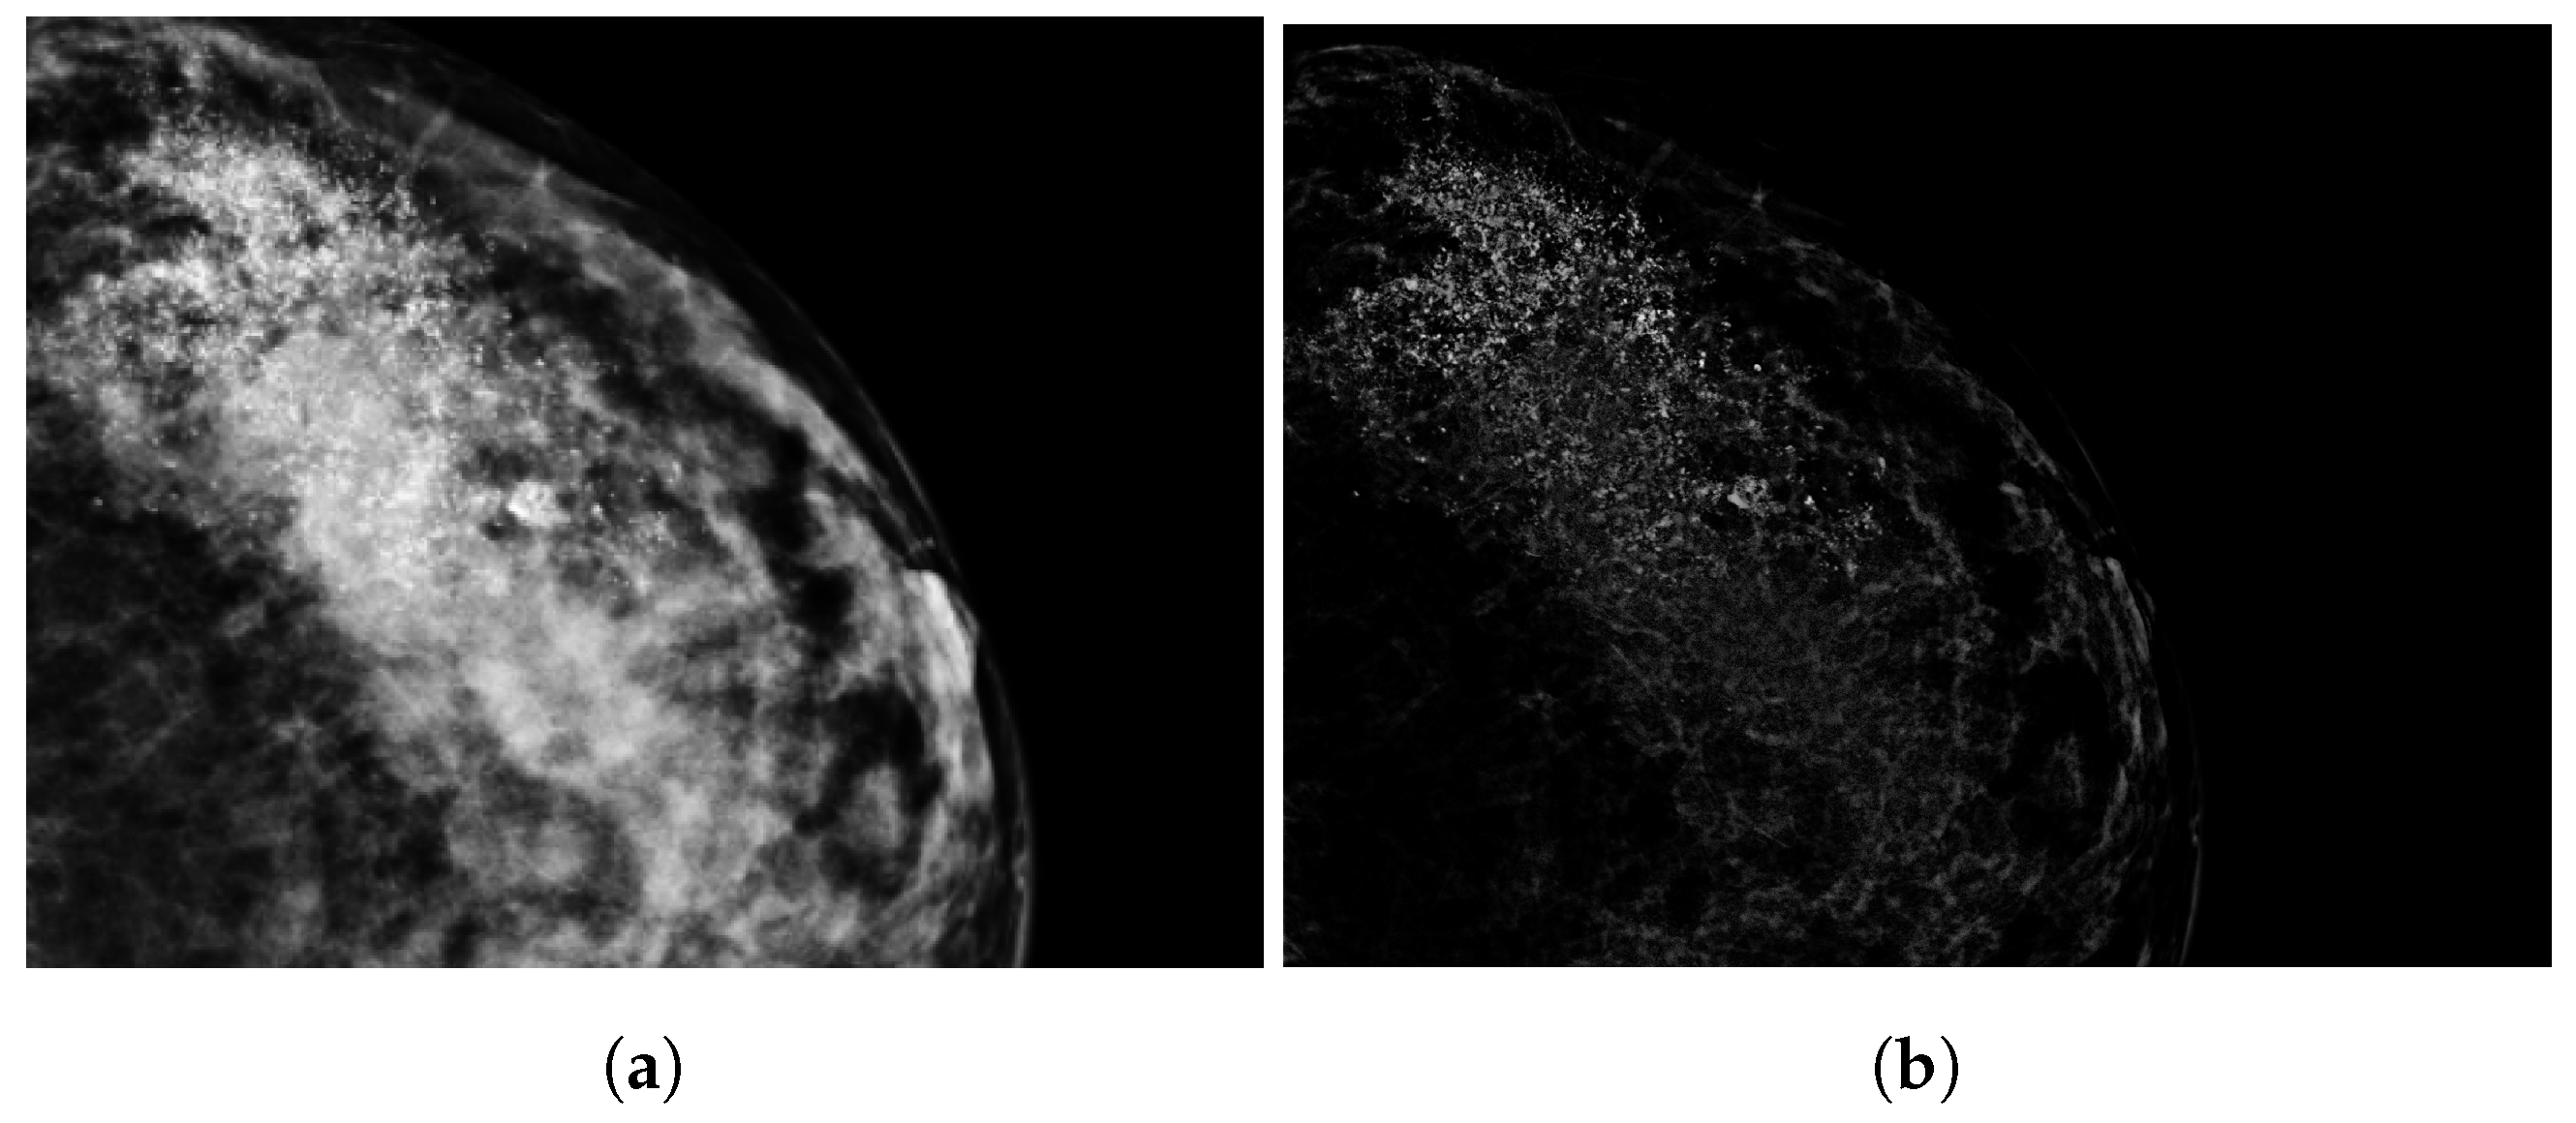

2.3. Tumor Segmentation